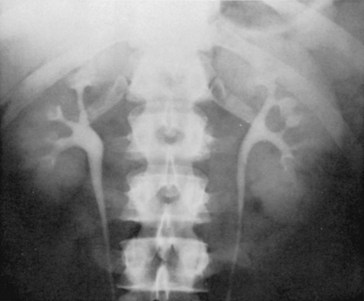

On close examination, it is clear that there is significant variation in the anatomy of the renal collecting system (Figs. 1-41 through 1-43). Number of calyces, diameter of the infundibuli, and size of the renal pelvis all vary significantly among normal individuals. Even in the same individual, the renal collecting systems may be similar but are rarely identical. Because of this variation, it can be difficult to distinguish pathologic from normal on the basis of anatomy alone. Instead, it is demonstrated dysfunction that is necessary to make the diagnosis of a pathologic anatomic formation within the renal collecting system.

Figure 1–42 Significant variation between two normal renal pelves, demonstrated by excretory urography. A, Large, extrarenal pelvis. B, Narrow, completely intrarenal pelvis, barely larger in caliber than the ureter.

Figure 1–43 Examples of normal variations in the architecture of the renal collecting system, demonstrated by excretory urography. A, Absence of calyces. B, Minor calyces arising directly from the renal pelvis. C, Megacalyces. D, “Orchid” calyces. E, Multiple minor calyces and nearly absent renal pelvis.